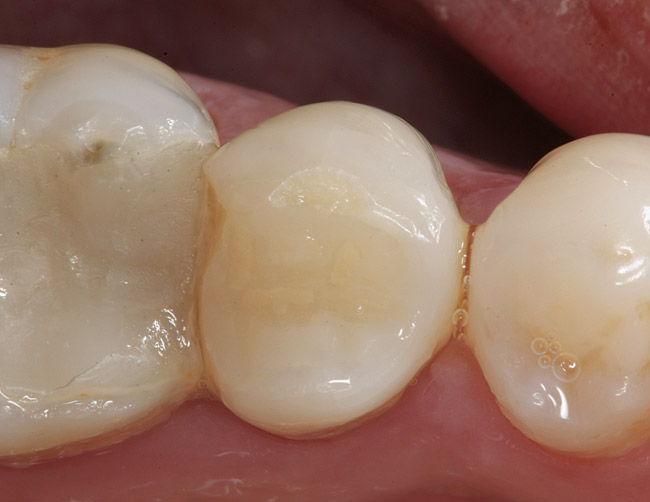

Replacement of existing restorations is responsible for 75% of all operative dentistry.15,19 The reasons for placement and replacement of restorations of direct restorative materials include: primary caries (Figure 1 and Figure 2); recurrent caries (Figure 3); poor margins (Figure 4 and Figure 5); restoration fracture (Figure 6 and Figure 7); tooth fracture (Figure 8); esthetics (Figure 9); non-carious tooth structure lost (attrition, abrasion, abfraction, erosion) (Figure 10); and pain/sensitivity.

Figure 5  Defective margins. Mandibular second molar with a Class II composite resin with a defective facial–gingival margin.

Figure 5